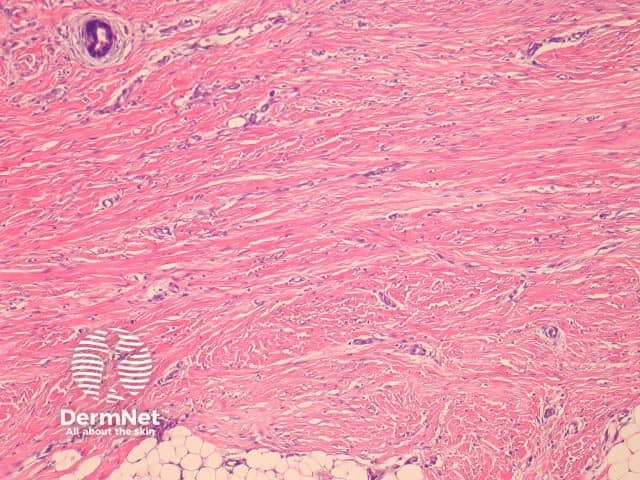

Fibroblastic connective tissue naevus is situated primarily in the reticular dermis, and often shows extension into the superficial subcutis (figures 1, 2). There may be a mild papillomatous epidermis. The lesional cells are bland spindle-shaped fibroblastic/myofibroblastic cells with indistinct pale eosinophilic cytoplasm and tapering nuclei, with no significant cytologic atypia or pleomorphism (figures 3, 4). These cells form short fascicles with no particular orientation to the overlying epidermis and are associated with a loose stroma composed of mainly delicate or wispy collagen bundles (figures 3, 4).

The lesion cells show variable expression of CD34. Smooth muscle actin shows variable positivity. FISH studies fail to reveal the PDGF/Col translocation seen in dermatofibrosarcoma.